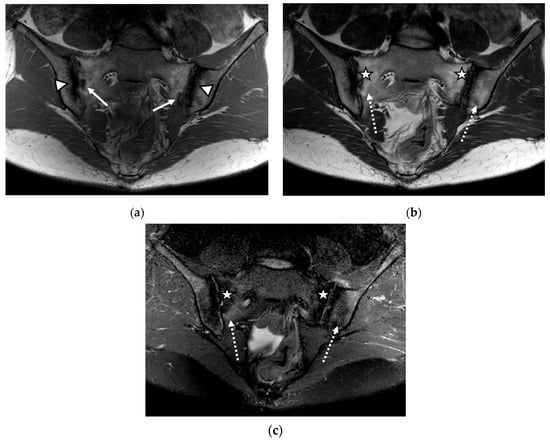

We evaluated 68 sacroiliac joints. The prevalence of MRI-detected abnormalities is presented in Table 2. The results of the SR were considered as the reference data. Inflammatory and structural changes were detected on the MRI sequences of the sacroiliac joints. The most frequently encountered inflammatory change, both on the left and right sacroiliac joint, was the presence of bone marrow edema (44.11–58.82%), followed by enthesitis (17.64–26.47%) and synovitis (11.76–17.64%). Regarding structural changes, the most prominent was subchondral sclerosis (50–59.37%), followed by erosions (35.29–41.17%), joint space narrowing (38.23%), fat metaplasia (17.64–23.25%), and backfill (11.76–20.58%) (Figure 1, Figure 2 and Figure 3).

Figure 1.

The magnetic resonance imaging (MRI) examination of the sacroiliac joints revealed narrowing of the sacroiliac joint spaces with bilateral marginal bone erosions (continuous arrow), bilateral subchondral sclerosis (arrowhead), and increased fat metaplasia (star), with minimal diffuse adjacent bone marrow edema (dotted arrow): (a) T1-weighted sequence; (b) T2-weighted sequence; (c) short tau inversion recovery (STIR) sequence.